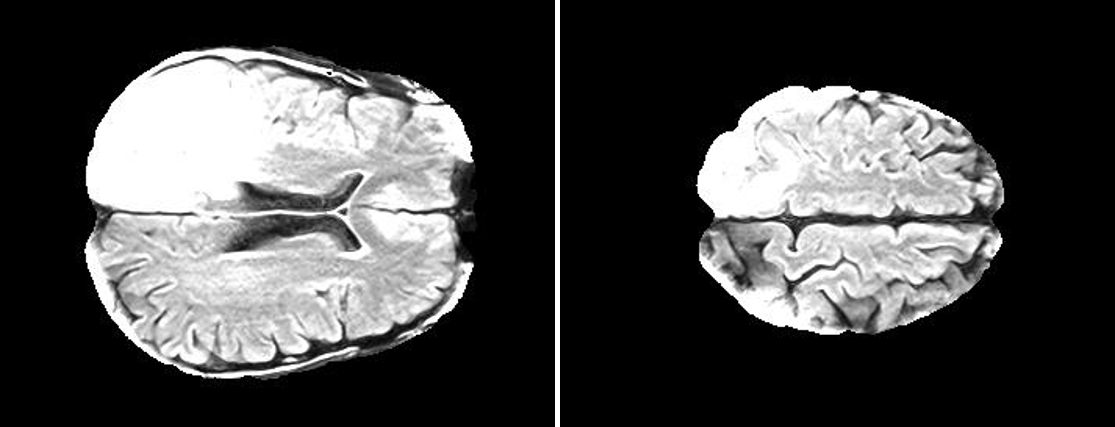

In order to make our results comparable, the analysis 2 and 3 were executed by using a public freely available dataset accessible via The Cancer Imaging Archive (TCIA) Clark et al. (2013). In details, the dataset includes DICOM files of 20 subjects from different sites with primary newly diagnosed glioblastoma who were treated with surgery and standard concomitant chemo-radiation therapy (CRT) followed by adjuvant chemotherapy. The sequences are T1-weighted (pre and post-contrast agent), FLAIR, T2-weighted, ADC, normalized cerebral blood flow, normalized relative cerebral blood volume, standardized relative cerebral blood volume, and tumour masks (i.e., ROIs) Schmainda and Prah (2018); Ellingson et al. (2009). Fig. 1 shows two among the 2D slices contained in the dataset and extracted from FLAIR. Each patient is described by two MRI exams: within 90 days following CRT completion and at progression. At the best of our knowledge, in this paper the dataset is used for the first time for ML experiments Schmainda et al. (2018). The following preprocessing steps were performed before running the analysis:

The dataset contains for each patient two MRI exams: the exams were recorded within 90 days following CRT completion and at progression, for now on ”pre" and ”post". For each patient the topological features (i.e. Euler characteristics, persistent entropy at H0 and H1 and generator entropy) were computed on the 2D slices of FLAIR. Welch’s t-test is used for comparing the mean of the topological descriptor computed over the ”pre" and ”post" set of images. Fig.:3 depicts of two FLAIR slices extracted for the same patients within 90 days following chemo-radiation therapy (CRT) completion and at progression.